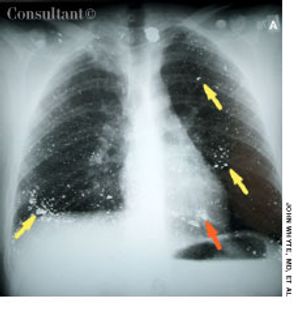

A minimally responsive 26-year-old man was brought to the emergency department after being found in his home by a friend. A suicide note lay next to his body. The patient had a history of depression.